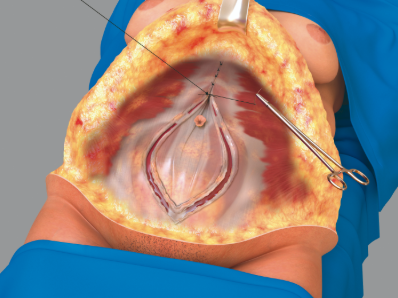

The WRAFA technique involves raising the suprafascial abdominal flap while sparing the umbilical stalk, as in traditional abdominoplasty. Once the flaps have been raised, a bilateral longitudinal curvilinear incision is made in the anterior recti sheaths with the widest point at or slightly above the level of the umbilicus. This point is located over the medial, central, or lateral third of the rectus muscle, always medial to the linea semilunaris (Figure 1). Each curvilinear incision is then directed toward the xyphoid and pubic areas. The lateral borders of this incision are then medialized to create a new linea alba over the midline, thus imbricating the medial recti muscle posteriorly and pulling in-block the lateral recti, external and internal obliques, and transversus abdomini muscles medially. The original linea alba is automatically retracted posteriorly and the navel is deepened (Figures 2-7). A new, strong linea alba is created.

Figure 1. Incision of the anterior rectus sheath (rectus fascia partition) in a fusiform shape at variable distances between the medial border of the rectus muscle and the linea alba. The width around the umbilicus is 12 cm.

Figure 2. Image of the same surgical case as Figure 1 demonstrating the myofascial closure and creation of a new linea alba.